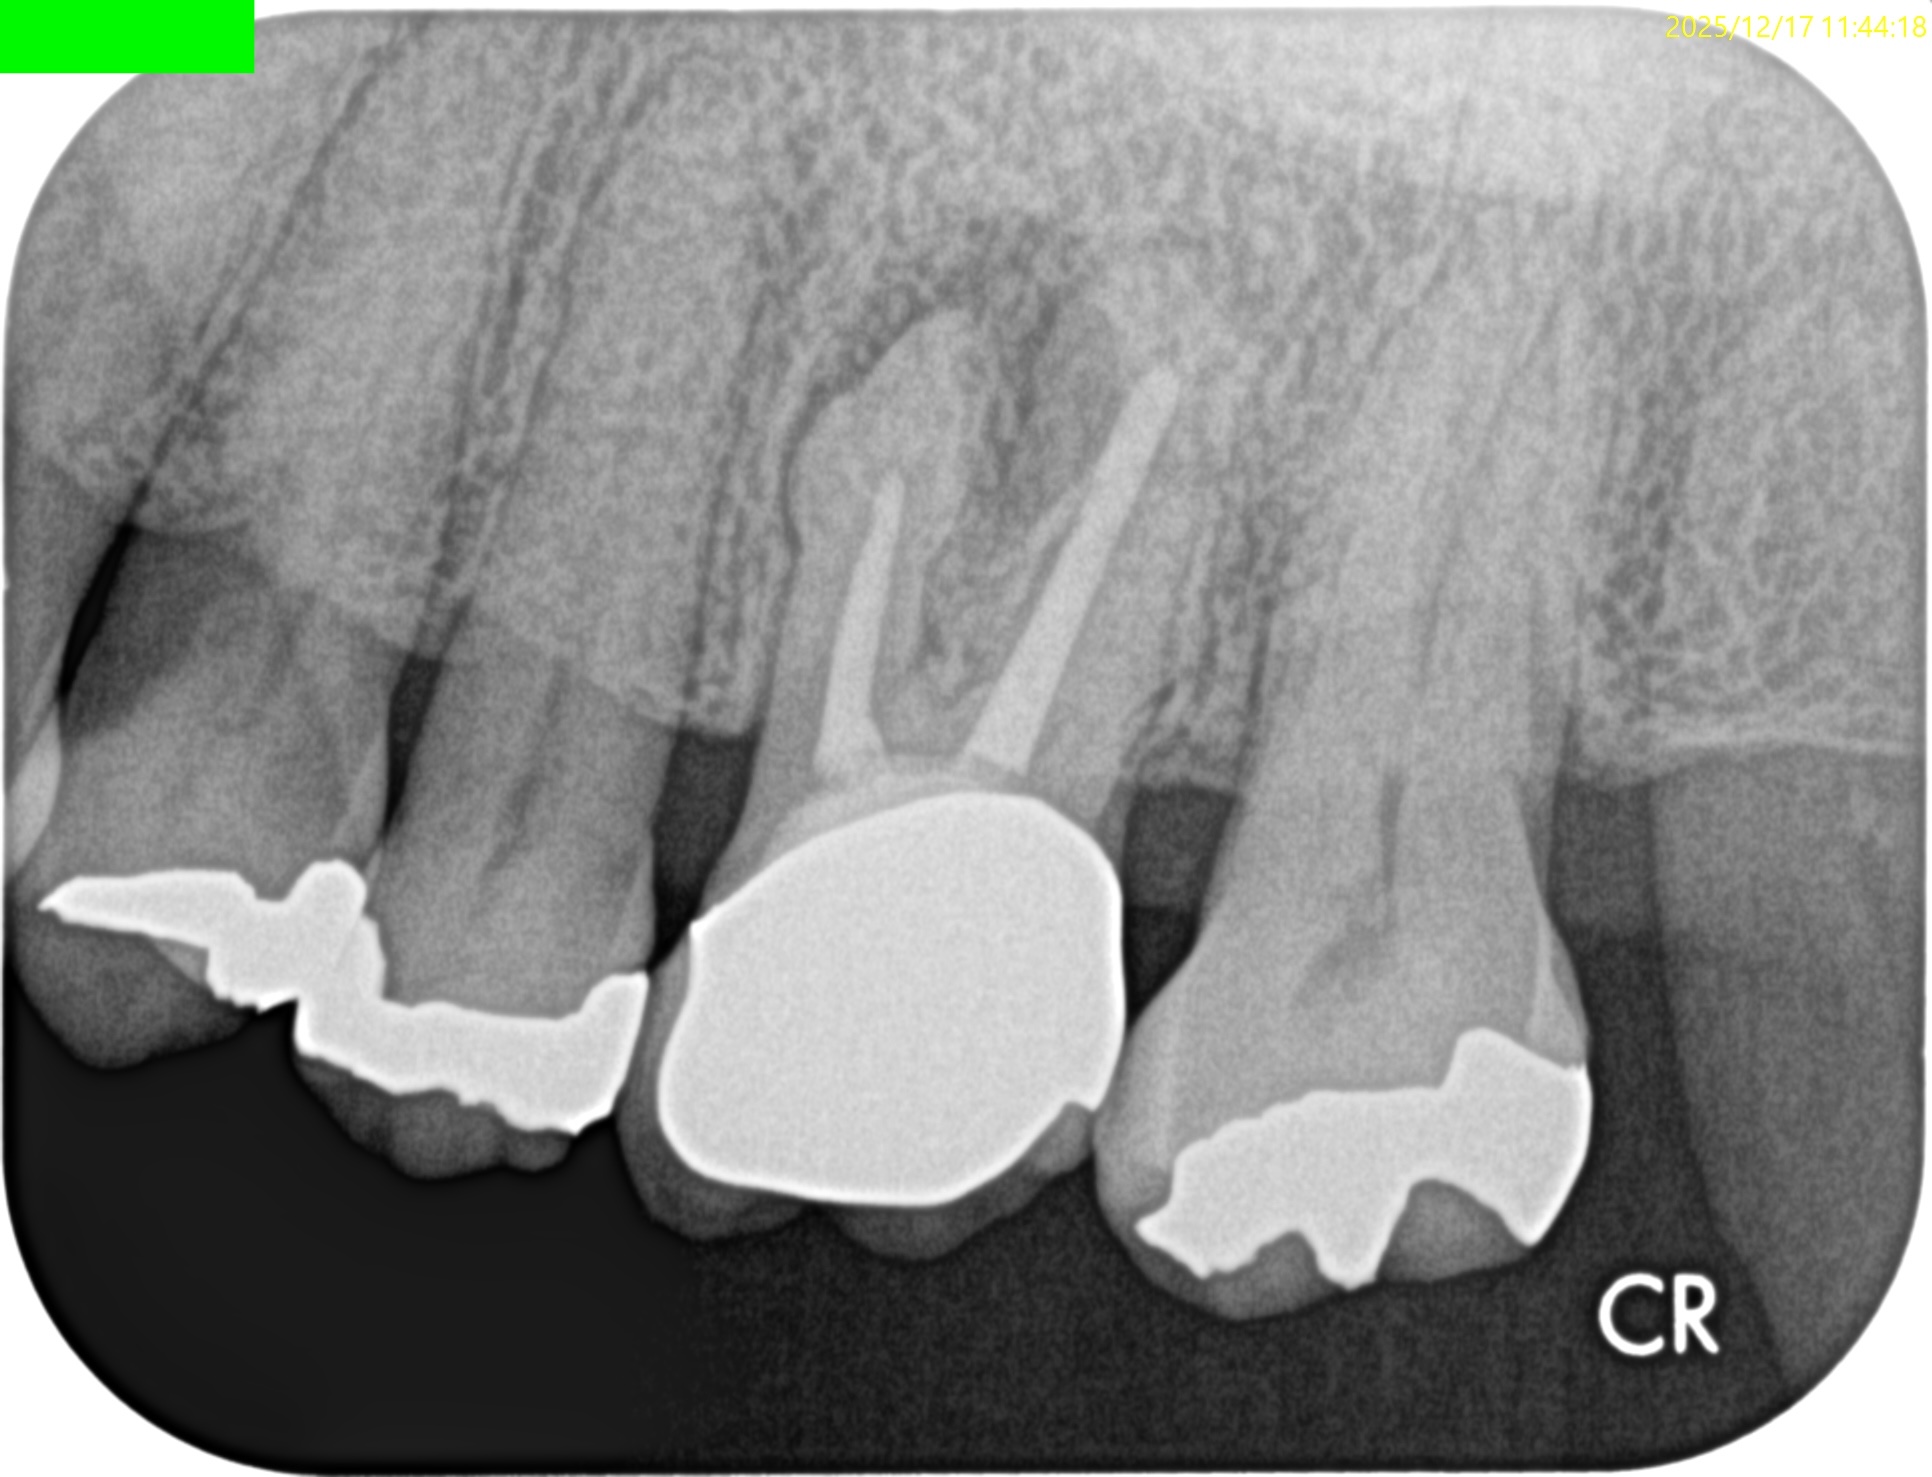

MB

DB

P

MB,DBは石灰化が進み再根管治療で穿通は不可能であろう。

故にここはApicoectomyだ。

が、P根は

作業長が16~18mm程度であるが

Apical Foramenまで根管充填できていないし、シーラーパフもない。

さておき、この同意書のPAではMB,DB,Pに根尖病変があるように見える。